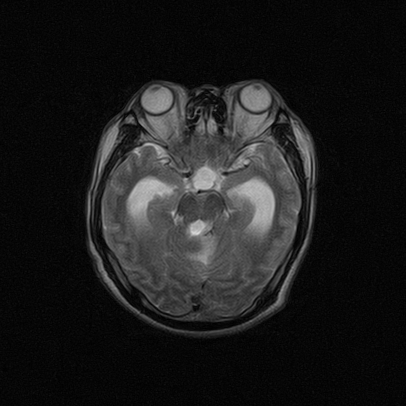

标题: MRI2064:少见病例。男性52,视力下降多年。 [打印本页]

标题: MRI2064:少见病例。男性52,视力下降多年。

四脑室区见混杂信号占位影,脑室系统扩张明显,临近结构显著受压称位,患者52岁,多考虑室管膜瘤可能性大

考虑第四脑室室管膜瘤并阻塞性脑积水。

应该是来源于小脑蚓部的占位,如血管母细瘤或星形细胞瘤

小脑血管母细胞瘤.并外压性脑积水.

小脑蚓部胶质脑膜瘤突入四脑室;肿瘤内见血管流空信号和钙化信号.

比较典型的脉络丛乳头状瘤并脑积水,鉴别小脑蚓部血管母细胞瘤。